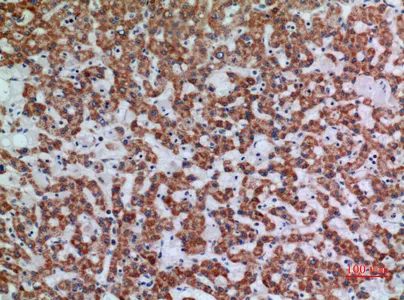

Mucin 1 Rabbit Polyclonal Antibody

Cat: APRab14238

Size1:50μl Price1:$118

Size2:100μl Price2:$220

Size3:500μl Price3:$980